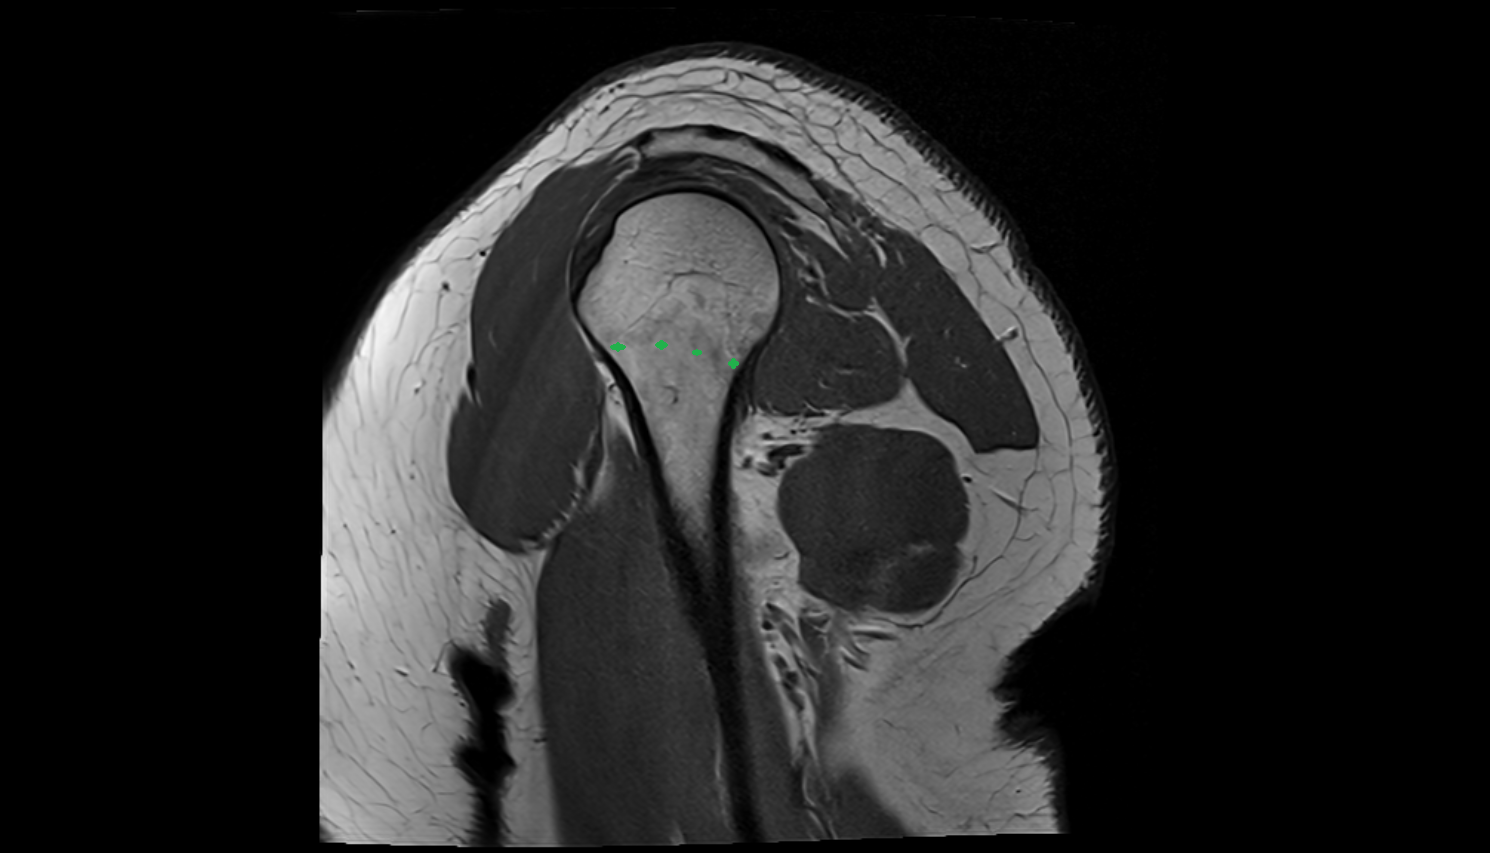

- Glenoid fossa

- Humerus

- Head of humerus

- Supraspinatus tendon

- Subscapularis tendon

- Glenoid labrum

- Glenohumeral joint capsule

- Adipose tissue (Shoulder)

- Subacromial space